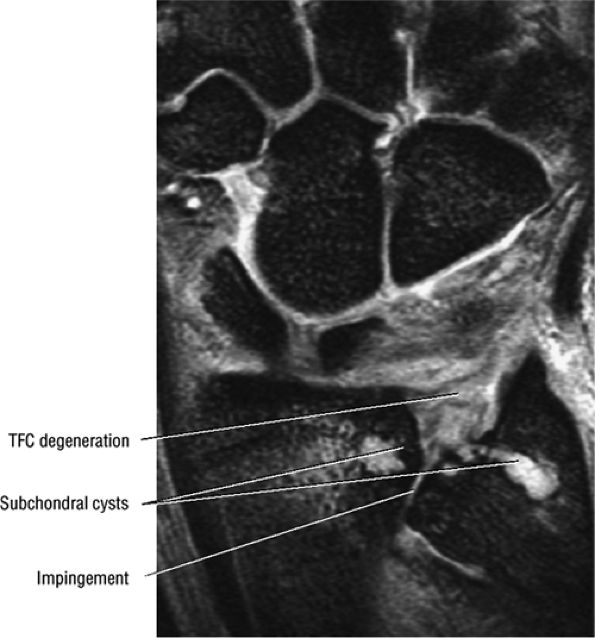

![]() |

FIGURE 10.55